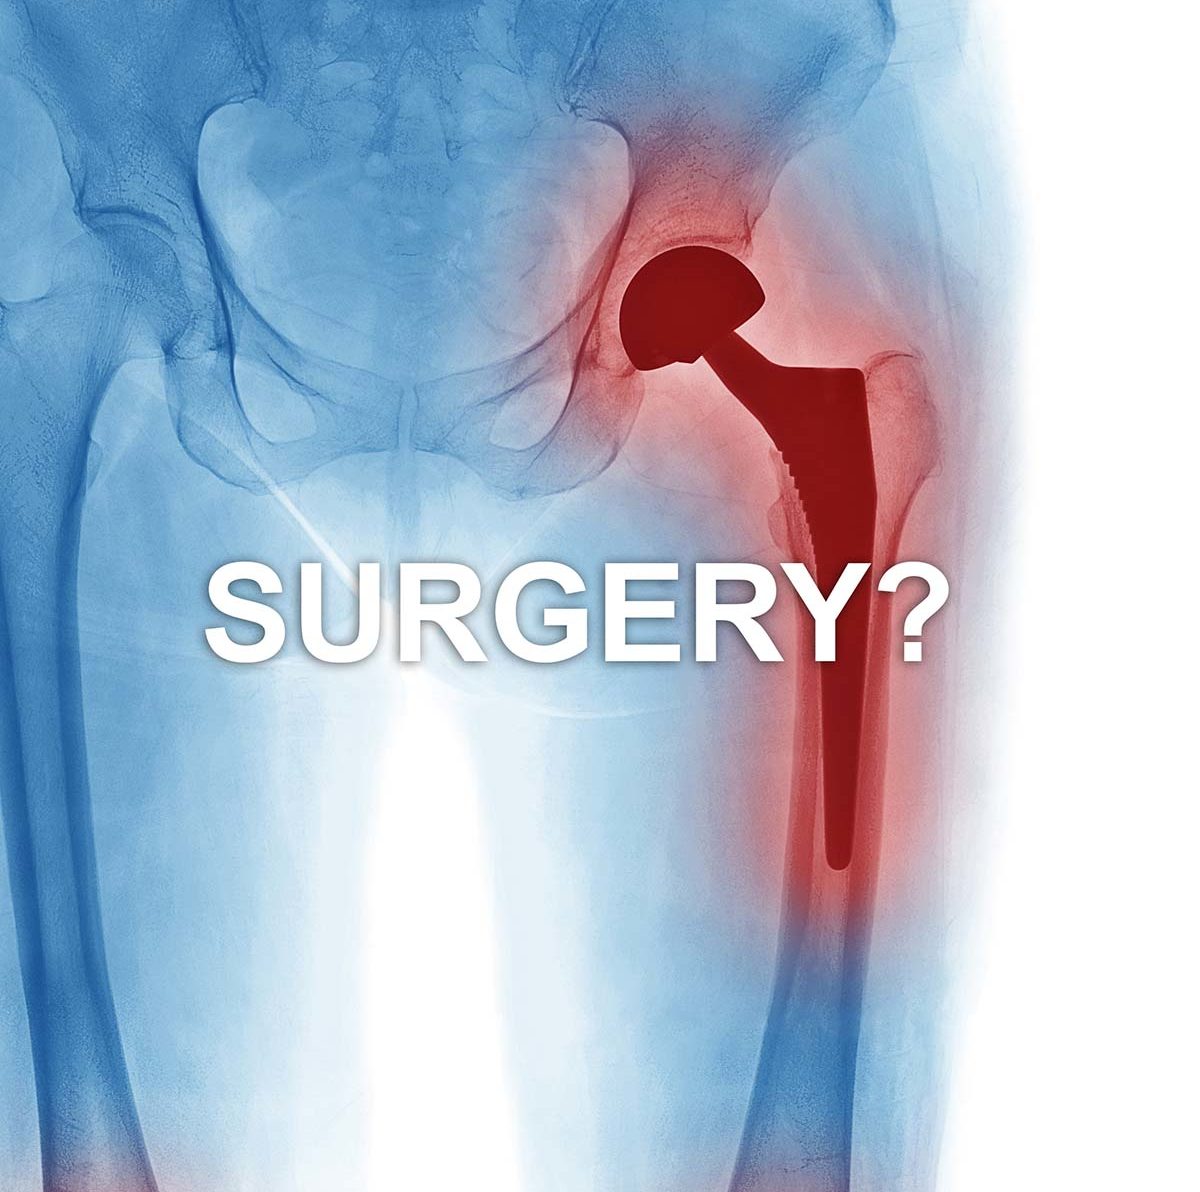

Hip Pain Treatment Without Surgery . Physical therapy, injections, and surgery may be needed for more chronic or complicated causes of hip pain. Conservative measures like pain relievers and home remedies can be used for a sudden, isolated injury. finding the right treatment to relieve hip pain often depends on what's causing it. With some conditions, it is possible. A physiotherapist can design a personalised program. Read a special health report from harvard medical school for more strategies and information.